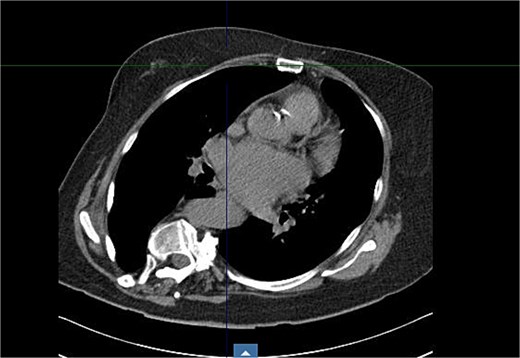

Preoperative imaging highlighted this significant spinal deformity and its impact on cardiac orientation and accessibility (Fig. 3). The scoliosis increased the complexity of the surgery, necessitating customized operative strategies. The patient underwent minimally invasive MVR and septal myectomy through a right mini thoracotomy. A mechanical valve was selected as a redo would be near impossible due to the cases uniqueness and inherent difficulty. Operative technique involved a 5 cm skin incision on the right upper breast at the 2nd ICS for a working port (Fig. 4), with additional ports in the 2nd and 4th ICS for camera and CO₂ venting. Extracorporeal circulation was established via femoral–femoral bypass through a groin incision to access the left femoral vessels for cannulation.